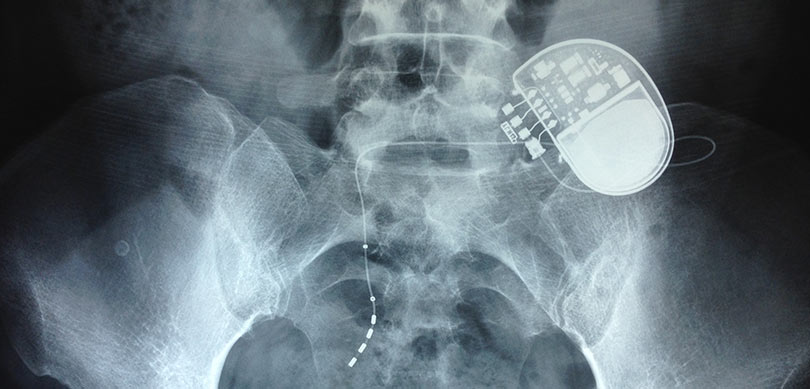

O neuromodulador sacral é um dispositivo que se assemelha a um “marcapasso” (embora seu funcionamento seja diferente deste). Um eletrodo é implantado no nervo S3 por punção na região lombar. Um estimulador temporário permanece por 1 a 2 semanas. Caso o paciente apresente melhora do quadro clínico, o gerador definitivo é colocado sob a pele.

O neuromodulador sacral é semelhante a um marcapasso. Esse aparelho é colocado em um nervo que vai em direção à bexiga com o objetivo de modular o órgão, de modo que este fique menos sensível, mais relaxado e bloqueie contrações involuntárias, cessando a incontinência urinária e a urgência em urinar.

O aparelho pode ser implantado em duas etapas. Na primeira, é colocado um eletrodo que estimula o nervo desejado do lado de fora. Este equipamento é externo e temporário. Se o paciente tiver uma boa resposta e apresentar melhora nos sintomas, ele volta ao centro cirúrgico e, através de uma pequena incisão na região lombar, é colocado o neuromodulador sacral, com uma bateria que dura de 5 a 7 anos.